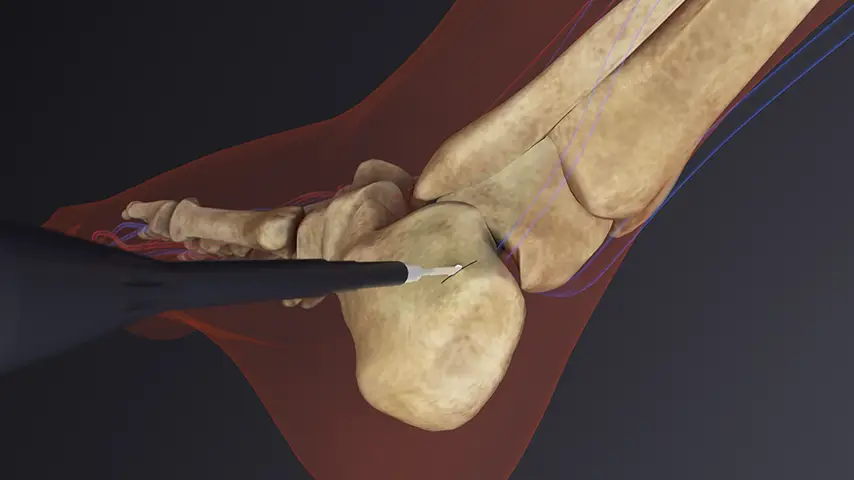

in Foot Surgery

Hallux Valgus Correction

Details

The controlled ultrasonic cut enables highly accurate metatarsal osteotomies, improving angular correction while minimizing soft-tissue trauma. This contributes to more predictable realignment and stable bone contact surfaces.

Recommended insert:

Calcaneal Osteotomy

Details

PIEZOSURGERY® allows deep and uniform cuts through the calcaneus with remarkable accuracy, improving the control of the corrective angle. Its soft-tissue safety is especially beneficial near tendons and neurovascular structures of the hindfoot.

Recommended insert: